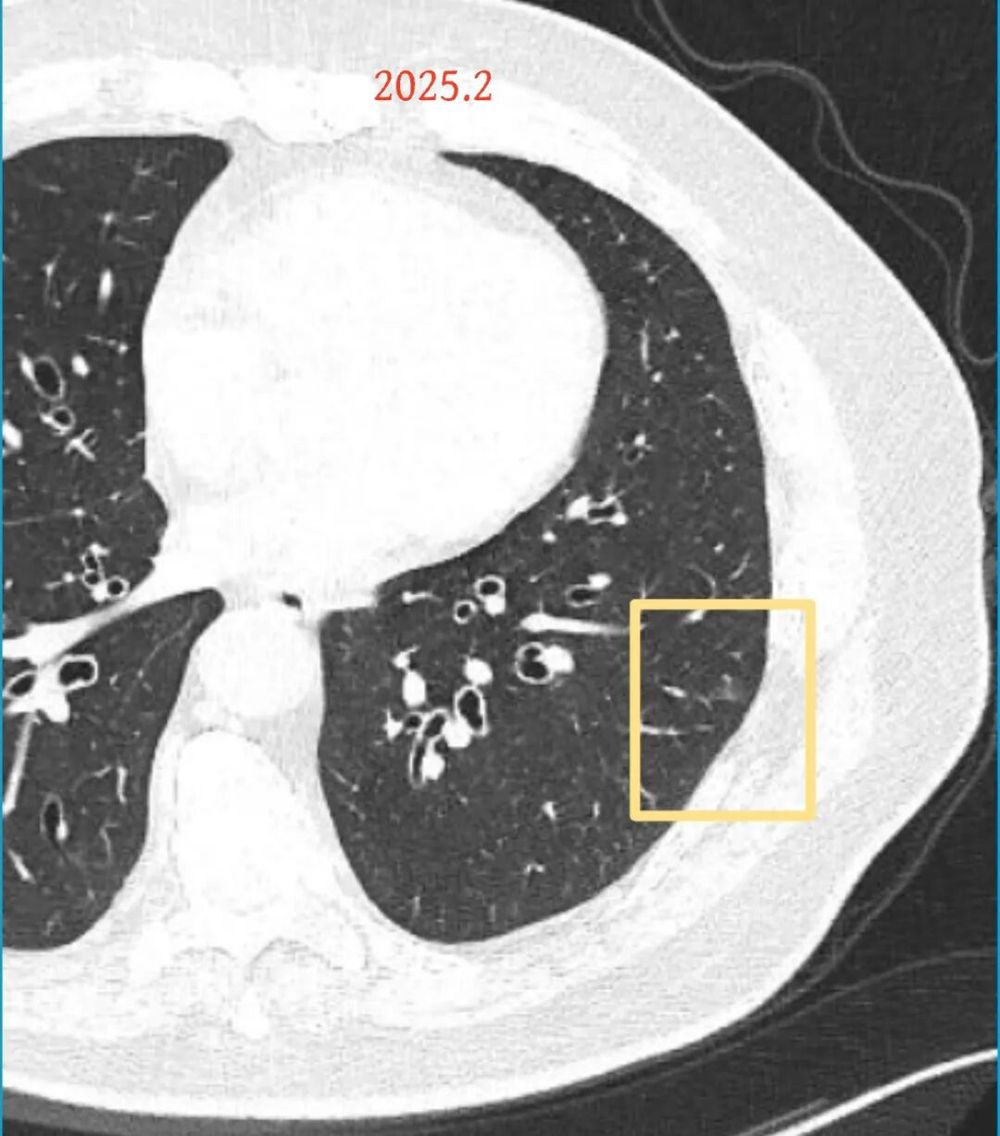

第一次问诊:2025.2

影像展示与分析:

方形的是25年的,红色的主病灶,磨玻璃密度伴少许略偏高点密度,但还说不上典型混合磨玻璃病灶,考虑原位癌或微浸润性腺癌可能性大;蓝色的轮廓与边界欠清,位置靠上叶中央,无法段切或楔切;黄色的多发均淡而纯,分布在两肺。圆形粉色的是主要的两处23年时的样子,对比说不上很明显进展。鉴于若手术得切肺叶,何况两肺他处仍的结节,年纪又74了。我倾向保守点,先6-9个月复查,等进展并风险增加再来考虑怎么办的事。意见供参考!

结友担心结节会短期内突然进展,我当时还告诉他不至于的:

我的想法是主病灶在右上叶,且多发,而且位置较深,若手术很可能要切且叶,虽考虑是肿瘤范畴的,但由于不管病灶A还是病灶B均仍是磨玻璃密度,没有纵隔窗可见的实性成分,在两肺多发病灶的情况下,适当保守点再随访下,待有进展并风险增高再干预也不至于影响预后。而且根据既往经验,磨玻璃密度的肺癌基本太会短时间内快速进展。